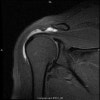

MRI : 충돌증후군(Impingement syndrome)

2. Rotator cuff tendinitis, calcification, tear

회전근개에 생기는 흔한 병리적 소견은 부종, 출혈, 만성염증, 섬유화, 미세건 파열, 완전파열 등으로 광범위하며, 주 발생기전은 건이 CA arch 밑으로 지나갈 때의 반복적인 기계적 마찰과 미세혈류의 장애입니다.